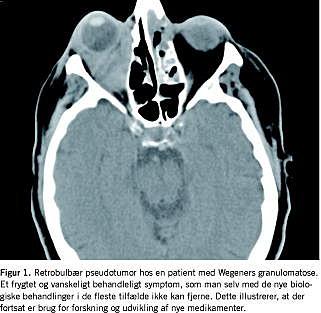

Anti-CD20-antistofbehandling af WG har været forsøgt mange steder, og anvendelsen af anti-CD20-antistoffer er beskrevet i flere mindre studier af retrospektiv og åben karakter. I alle studierne er der rapporteret om god effekt, og der er nu iværksat et internationalt prospektivt forsøg. Forhåbentlig kan dette være med til at definere, hvilke patienter med denne sygdom som responderer, idet resultater fra de mindre studier tyder på, at patienter med især retroorbitale manifestationer ikke havde behandlingsrespons med denne medicin [5, 6] (Figur 1).